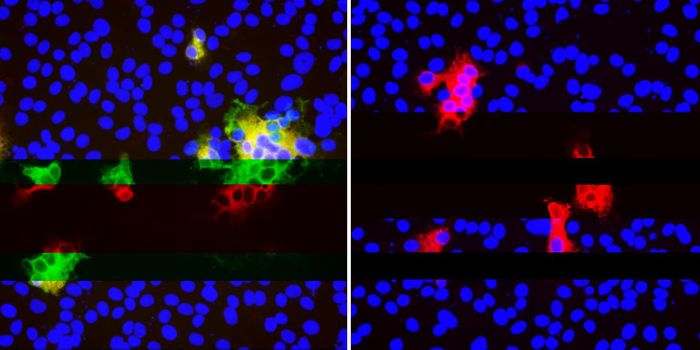

NOV 25, 2021ImmunologyInstead of flooding the body with antibiotics, what if we could program cells to fight off pathogens more effectively? T ...